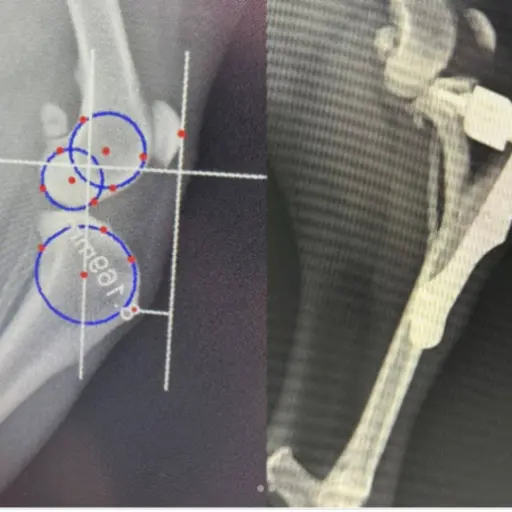

TTA Çapraz Bağ Kopuğu

Uzmanlık alanları arasında bacak ve kol kırıkları, travma sonucu kalça kırıkları, yüksekten düşme sonucu oluşan travmalar, kranial ve ön çapraz bağ kopmaları, parçalı pelvis kırıkları, eklemden kırıklar, kalça çıkıkları, distal radius ve ulna kırıkları ile doğumsal kalça problemleri gibi birçok ortopedik vaka yer almaktadır.